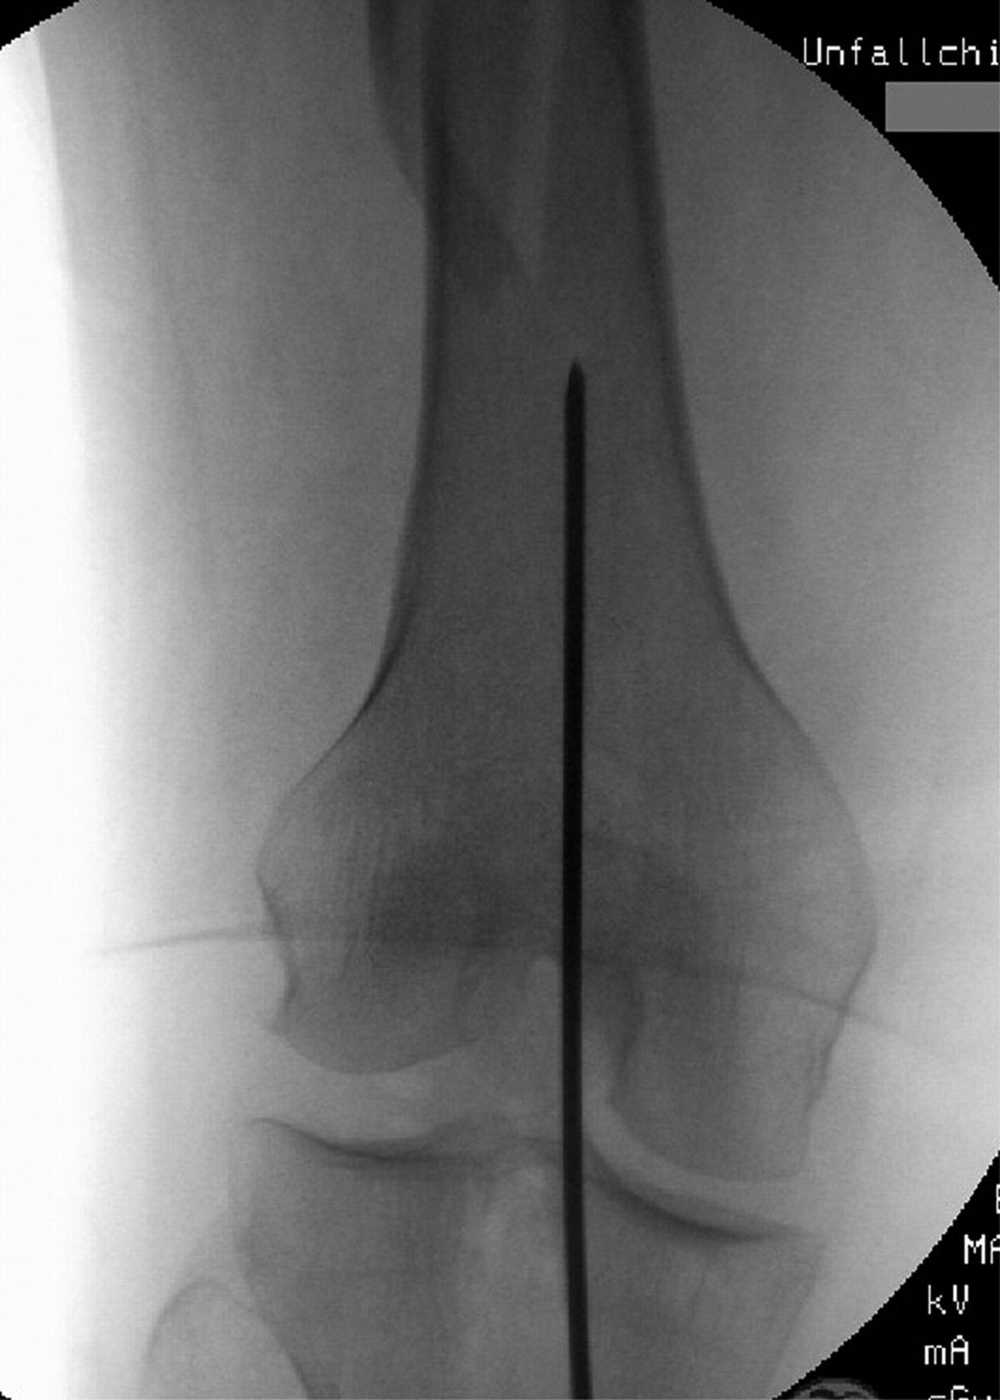

Kategorin omfattar osteosyntesmaterial för ortopedi, såsom skruvar, plattor, märgspikar med mera – produkter som används för stabilisering och läkning av frakturer samt rekonstruktion av skelettets strukturer.